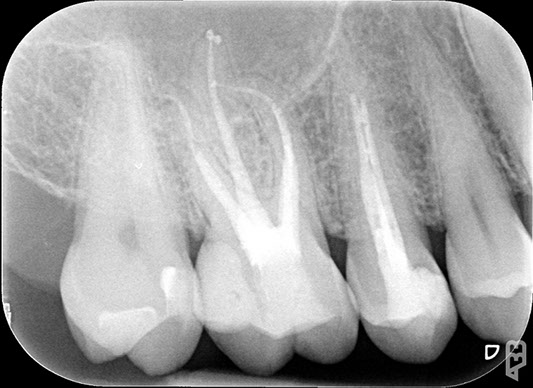

• otturazione di tutto l'endodonto mediante materiali termoplastici (guttaperca) e cementi biocompatibili

• controllo radiografico